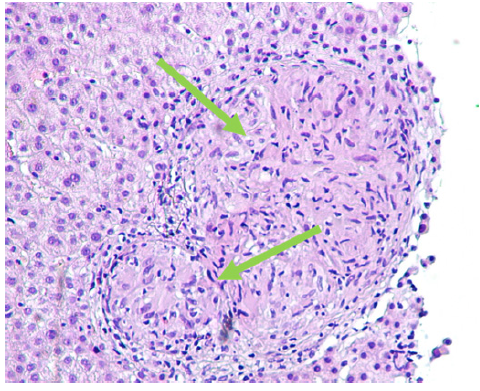

Abdominal ultrasound, contrasted tomography, and magnetic resonance cholangiopancreatography revealed mild hepatomegaly with a homogeneous liver and no other significant findings. Comprehensive study results were negative for infections, auto-immunity, heavy metal poisoning, metabolic diseases, and plasma cell dyscrasia (shown in Table 1). Despite the absence of respiratory symptoms, angiotensin-converting enzyme was elevated (200.7 U/L - normal range: 20-70 U/L). In this context, a chest radiological study was performed, revealing mediastinal and peribronchial adenopathies and a diffuse interstitial densification pattern in lung bases on computed tomography (shown in Fig. 1). Additionally, bronchoscopy identified whitish micronodules on the left lateral wall of the trachea and left main bronchus, with biopsies confirming non-caseating epithelioid granulomas. Immunophenotyping of bronchoalveolar lavage showed a CD4+/CD8+ lymphocyte ratio greater than 3.5. A liver biopsy was then performed (shown in Fig. 2), revealing multiple epithelioid granulomas located periportally and in the lobular areas, without necrosis. The histochemical study showed no evidence of microorganisms, including acid-fast bacilli (Ziehl-Nielsen) or fungal structures (PAS and Grocott); there was an absence of hyaline globule deposits, hemosiderin (Perls), and copper (rhodanine). In the immunohisto-chemical study, rare bile ducts were observed, and periportal he-patocytes exhibited an intermediate cell phenotype, suggesting chronic cholestasis. These findings were suggestive of HS.

Fig. 2. Liver biopsy revealing multiple epithelioid granulomas located periportally and in the lobular areas, without necrosis (see arrows) immunohistochemical study revealing rare bile ducts, and periportal hepatocytes with an intermediate cell phenotype, suggesting chronic cholestasis.